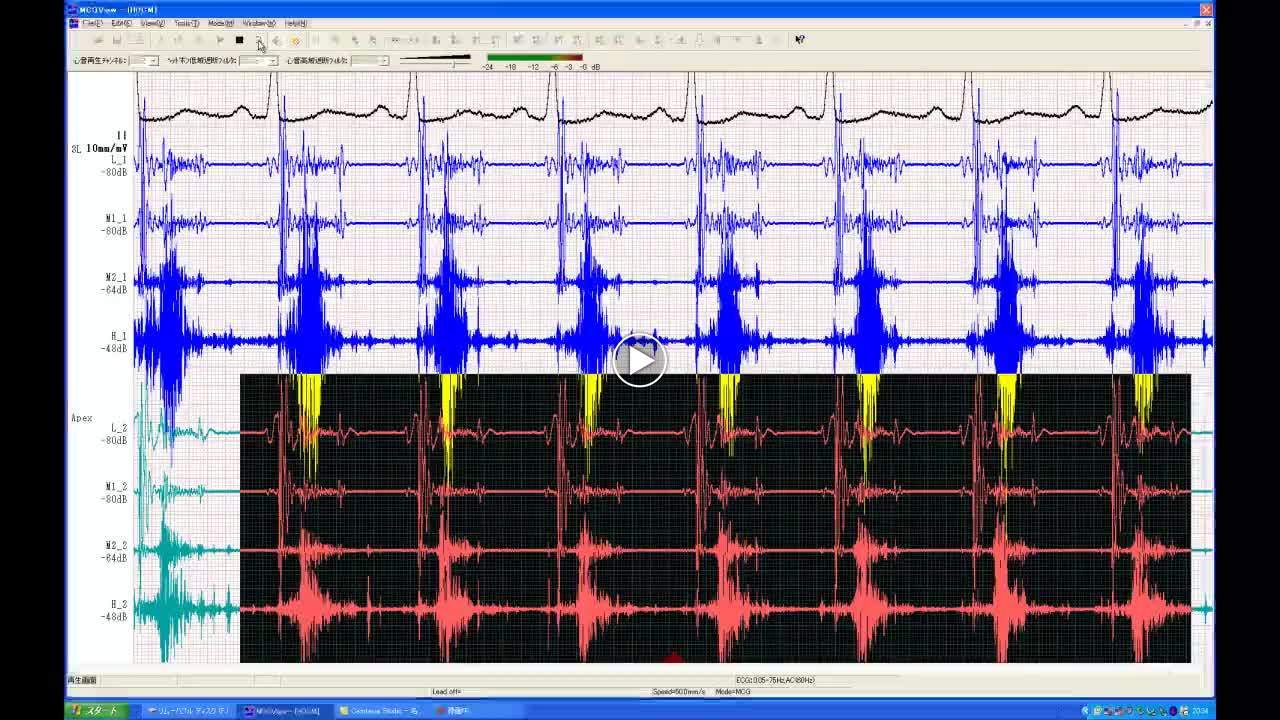

• 図4 心音 心尖